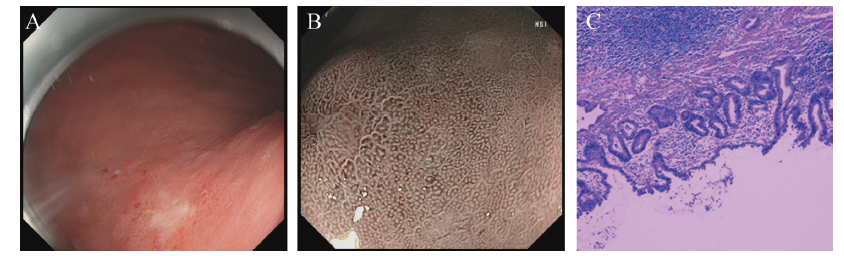

因患者第1次胃镜病理结果与胃镜下诊断不完全一致,为进一步明确病灶性质及病灶范围,再次行精查胃镜检查,镜下见胃体小弯侧后壁(胃体病灶)黏膜粗糙,局限黏膜不规则隆起,NBI+ME观察腺管和微腺管不规则,边界欠清,予病灶中央及四象限活检,贲门下方见片状黏膜粗糙,中央凹陷(图1A~C、E~G)。精查胃镜定点活检病理结果提示“贲门下方中央”黏膜内少量腺癌;“胃体病灶中央、口侧及肛侧” LGIN(图1D、H);Hp (-)。

图1 一例SMPEGC合并GCP患者精查胃镜检查及病理图

注:A为胃体近贲门病变远观图;B为胃体近贲门病变近观图;C为胃体近贲门病变NBI+ME图;D为胃体近贲门病变病理活检(HE染色,×100);E为胃体小弯病变远观图;F为胃体小弯病变近观图;G为胃体小弯病变NBI+ME图;H为胃体小弯病变病理活检(HE染色,×100)。